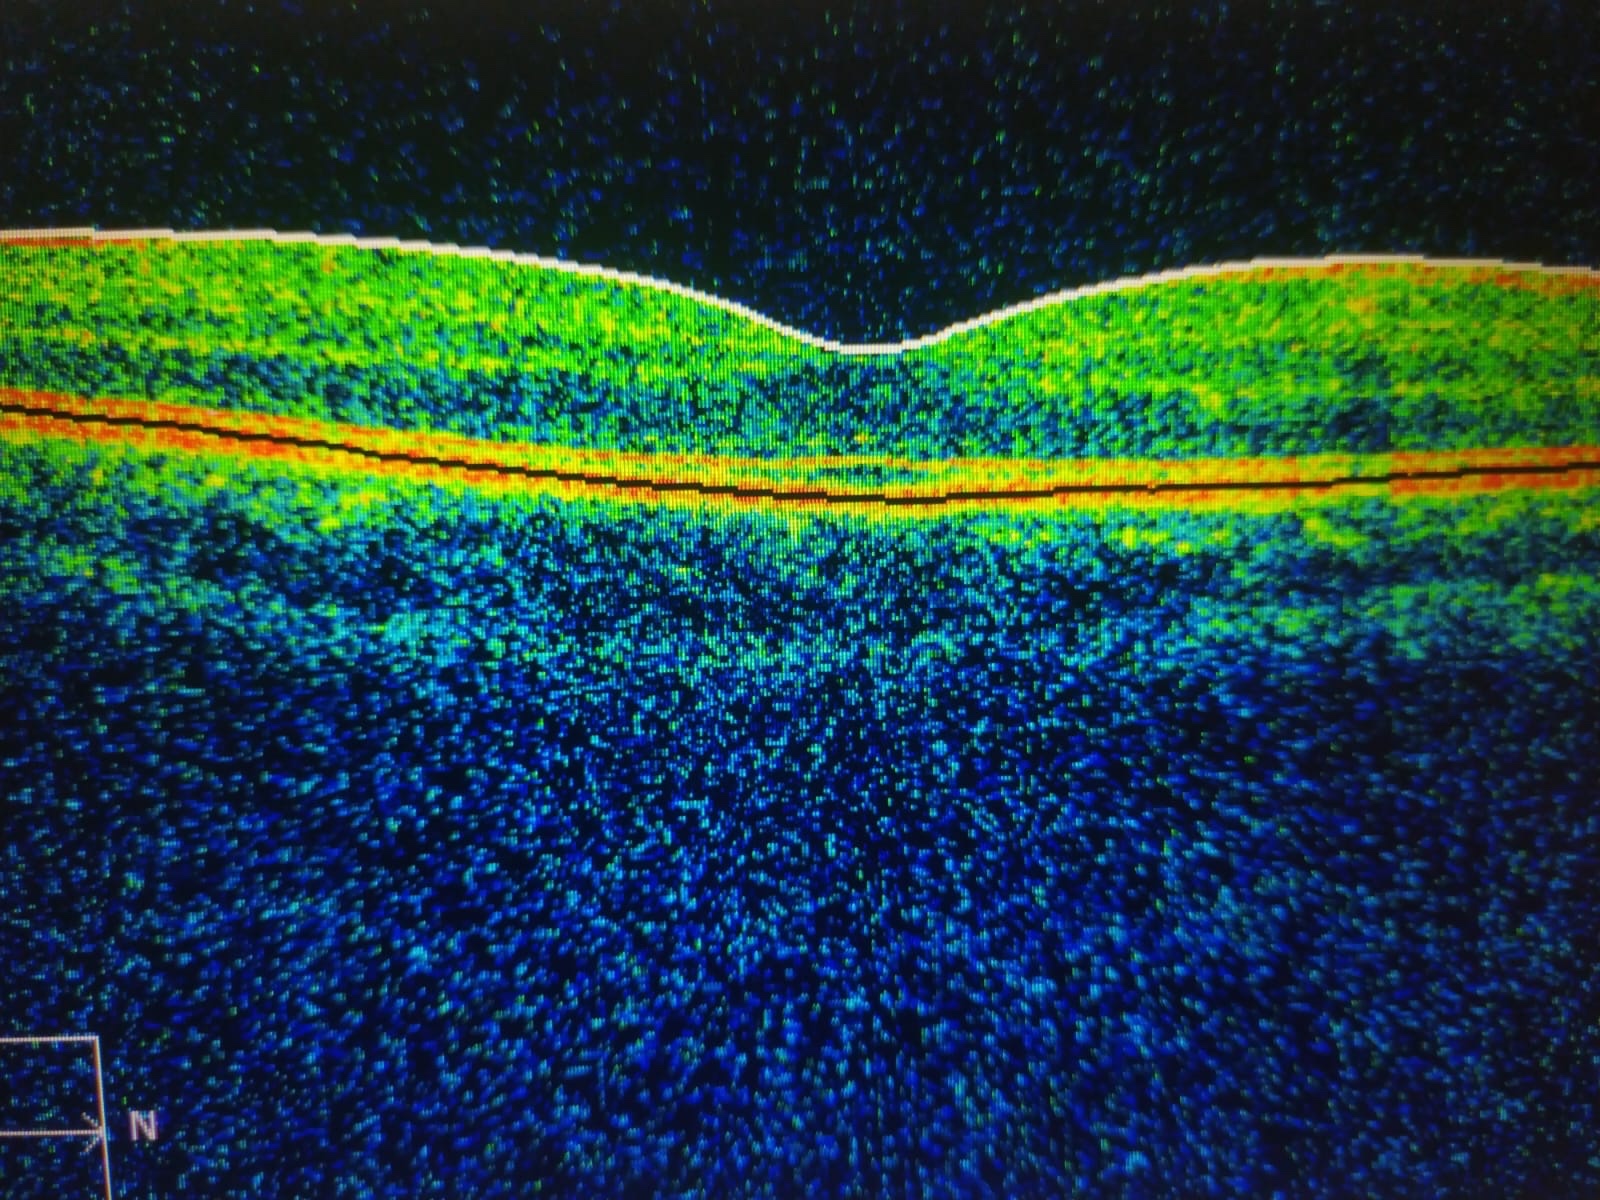

E d e m a m a c u l a r

OCT